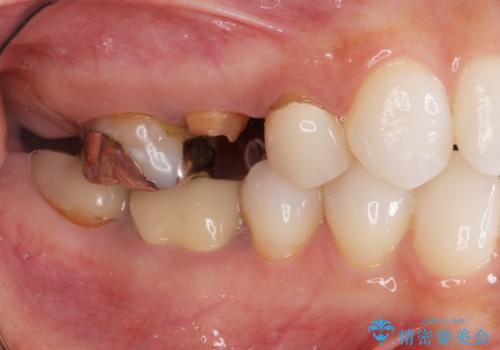

歯が割れているといわれた 奥歯にインプラントをしていきたい 全体的な治療